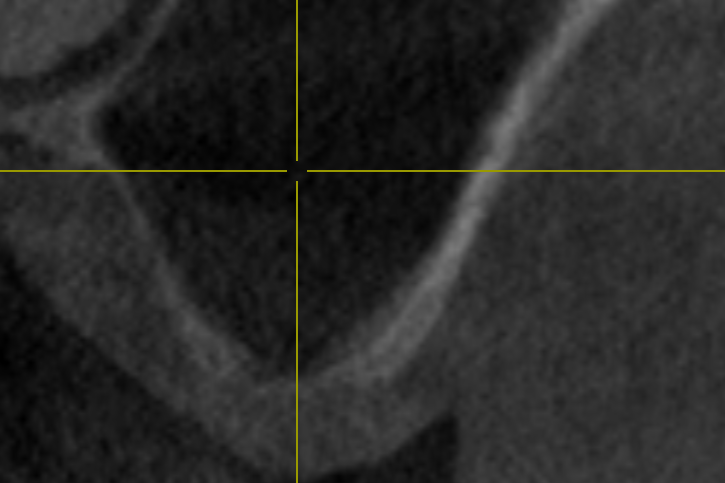

02/14 - Transversal section to determine depths of the sinus floor

Two-stage sinus lift with maxresorb® & collprotect® - Dr. S. Kistler